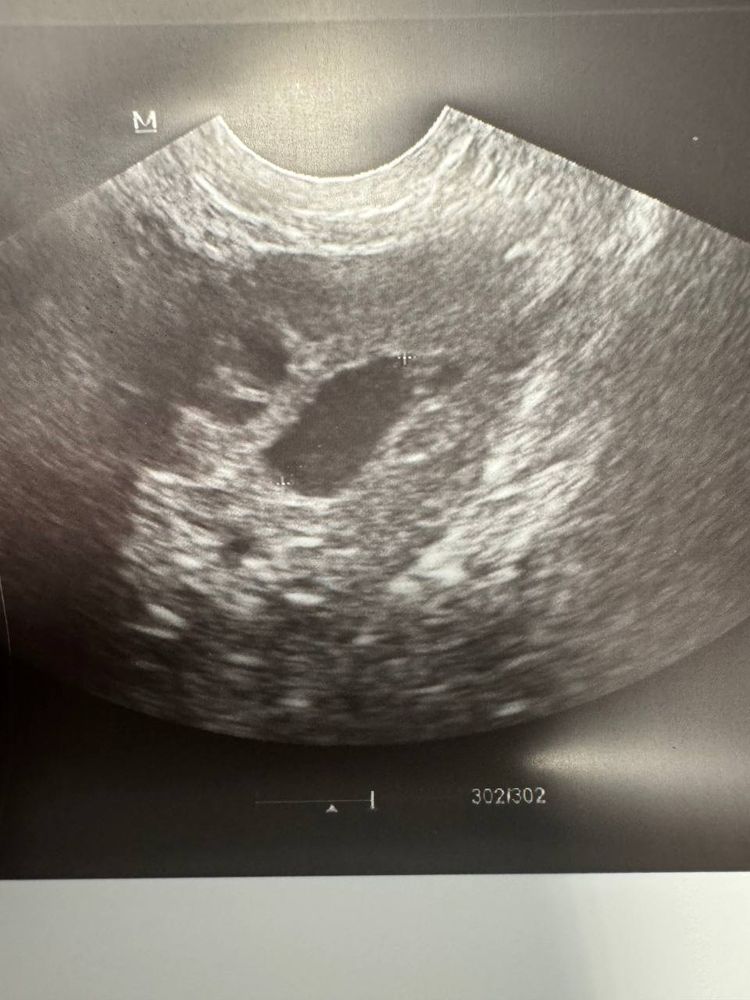

Limonchelka, да, ДФ был слева, но врачу УЗИ он не нравится) говорит, что это старый фолликул с прошлого цикла, скорее всего) Стеночки у него тонкие какие-то мол, да и форма овальная 😁 Я тоже склоняюсь к тому, что он персистентный) Болело тоже все слева: и поясница, и бок и низ живота. 😢 Видно будет, но есть ощущения, что это может быть из-за «фолликула» этого и придется вызывать месячные( Спасибо за ответ 🙏🏻